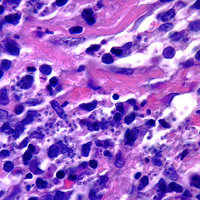

A sixteen-year-old teenage boy spent a month in the Amazon basin in Brazil. After returning

to the United States, he noticed a small indurated nodule on his forehead.

He treated the nodule with topical antibiotics. During the next

three months, the lesion did not heal, but became ulcerated and continued

to grow. The teenager visited his doctor who photographed the lesion

and performed a biopsy. Figure A is a photograph of the lesion

on the young man’s forehead. Figures B, C, and D

are Giemsa stained sections of the tissue that was sent to CDC for

identification/diagnosis. What is your diagnosis? Based on

what criteria?